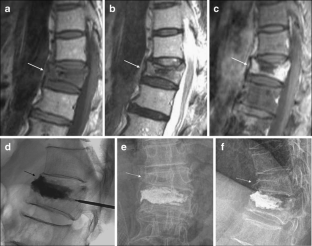

Fig. 2